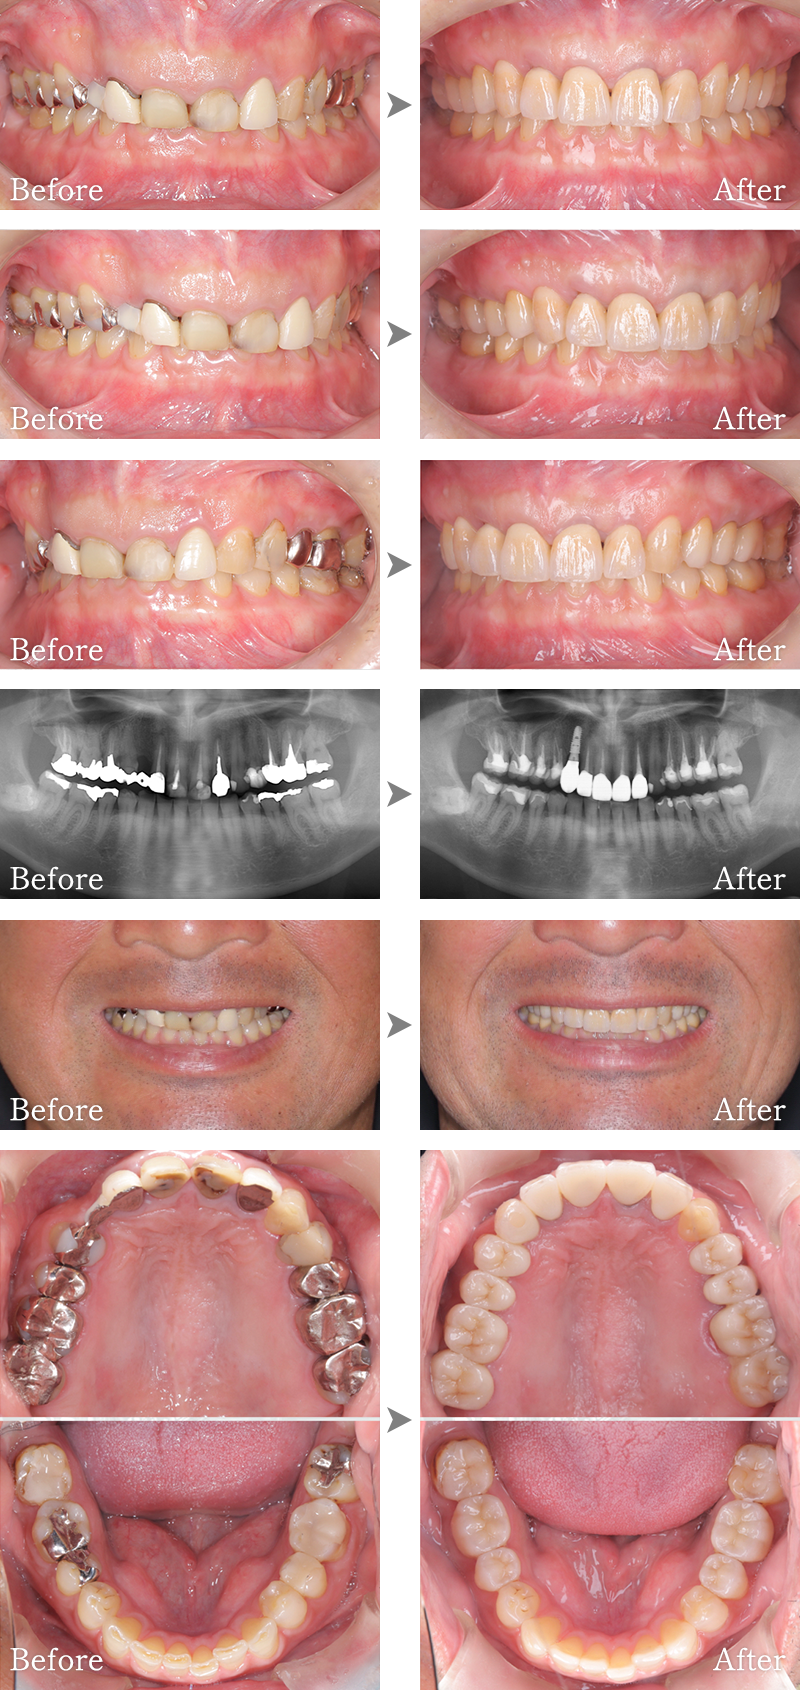

CASE4

骨格1級患者に対し、臼歯部にインプラント治療を行い咬合回復を行なった1症例

マークをスライドしてご覧ください

インプラント症例5

主訴 右側でうまく噛めない

治療内容 下顎臼歯部インプラント、咬合再構成、上顎矯正治療、セラミック治療

治療期間 約2年

費用 診断料:22万円(税込)

下顎顎臼歯部インプラント埋入手術:22万円(税込)×4本

セラミック補綴:22万円(税込)×4本

セラミック治療:11万円(税込)×9本

矯正治療:44万円(税込)